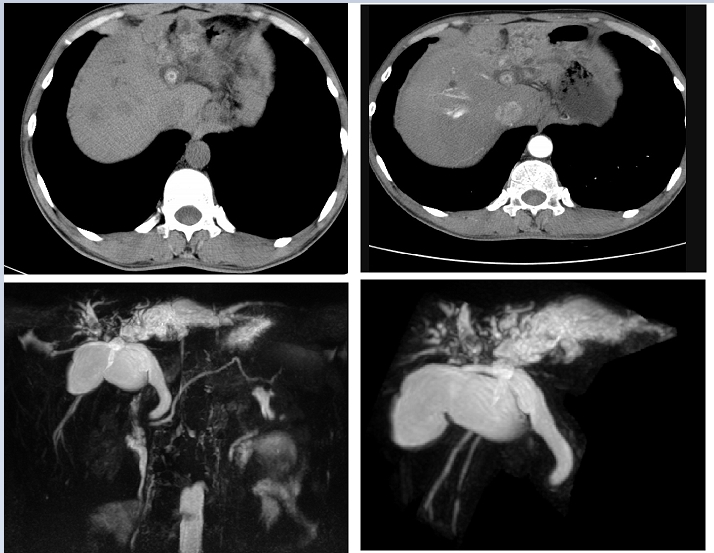

肝内胆管结石是我国常见而难治的胆道疾病,术后结石残留率在20%-40%之间。手术难度大,治疗比较棘手。近期,我院普外三科延学军团队收治一复杂肝内胆管结石病人,该病人以“间断右上腹部胀痛不适10年余”为主诉入院。该病人长期一直按胃病治疗,近2年来,症状加重,才引起重视。辗转多家医院,均因病情复杂,建议转院治疗。(该病人入院后相关检查结果如下:)

肝内胆管结石病因复杂,主要与胆道感染、胆汁停滞、胆管解剖变异、营养不良等有关。结石绝大多数为含有细菌的棕色胆色素结石,常呈肝段、肝叶分布,多见于肝左外叶及右后叶,与此两肝叶的肝管与肝总管汇合的解剖关系致胆汁引流不畅有关。肝内胆管结石易进入胆总管并发肝外胆管结石。

肝内胆管结石病理改变有:①肝胆管梗阻:可由结石的阻塞或反复胆管感染引起的炎性狭窄造成,阻塞近段的胆管扩张、充满结石,长时间的梗阻导致梗阻以上的肝段或肝叶纤维化和萎缩,如大面积的胆管梗阻醉终引起胆汁性肝硬化及门静脉高压症。②肝内胆管炎:结石导致胆汁引流不畅,容易引起胆管内感染,反复感染加重胆管的炎症狭窄;急性感染可发生化脓性胆管炎、肝脓肿、全身脓毒症、胆道出血。③肝胆管癌:肝胆管长期受结石、炎症及胆汁中致癌物质的刺激,可发生癌变。